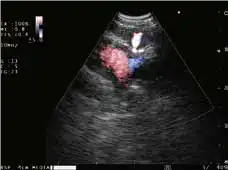

造影谐波EUS(CH-EUS)模式

CH-EUS模式采用谐波描出技术,可提示医生判断病变及其它异常生长。

与凸阵扫描超声内镜配套使用

THE-P模式 POWER FLOW模式 COLOR FLOW模式

H-FLOW模式 ELST模式